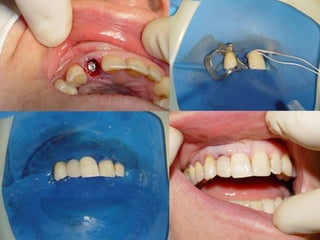

Avaliação Clínica no Momento da Instalação do ImplanteAparelhos especiais Osstell (mede por freqüência e ressonância)Avaliação Clínica (estabilidade)Torquímetro (mínimo 45 Newtons)Avaliação   radiográfica   ( durante   a instalação,  mede  a  distância   entre implantes e estruturas adjacentes)

Avaliação Clínica Após Período de Osseointegração Imobilidade ClínicaAssintomáticoAusência de imagem radiolúcida peri-implantarAusência de neuropatiaPerda óssea vertical inferior a 1,0 mm após o primeiro ano em  função, e  de   0,1 mm nos anos seguintes

Opções de PrótesePrótese Parcial Fixa Associado a RemovívelPrótese Parcial FixaPrótese Parcial RemovívelPrótese TotalPrótese Sobre Implantes	Unitária	Vários Elementos	Overdenture